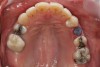

Figure 2a  Corticotomy SFOT. The patient presented with unesthetic anterior bridgework that was placed at age 14 to compensate for congenitally missing Nos. 7 and 10.

Figure 2a

Figure 2c  One week postsurgery with mesial buildups on Nos. 5 and 12 and thin pontics on archwire to conceal spaces during closure.

Figure 2c

Figure 2d  Prerestorative orthodontics was completed in 5 months. Final result 3 years, 4 months after completion.

Figure 2d